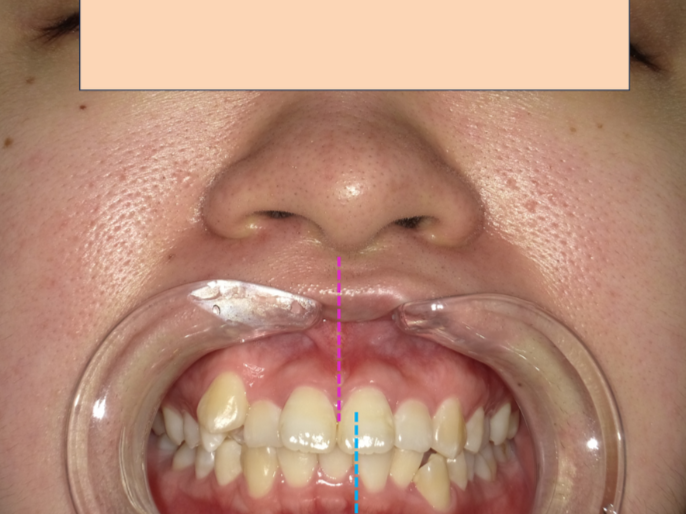

| 主訴 | 口元の突出感が気になる症例 |

この患者様は、歯の凸凹も気になるが、一番は口元の突出を改善したい、とのことでした。

この方の場合は上下の骨格の関係も二級関係(上顎が若干前・下顎が若干後ろに位置している)もありましたが、最も顕著だったのは、上下の前歯の歯の軸が上下ともに前に倒れていることでした。

患者様も顔が変わったって言われる!とおっしゃっていました。

矯正治療で、症例にもよりますが、口元の激変で整形級に変わる方もいらっしゃいます。(例えば口元は出ているが歯がすでに飛び出ていなくて、傾斜がない場合の方が口元を引くのむづかしくなります。)